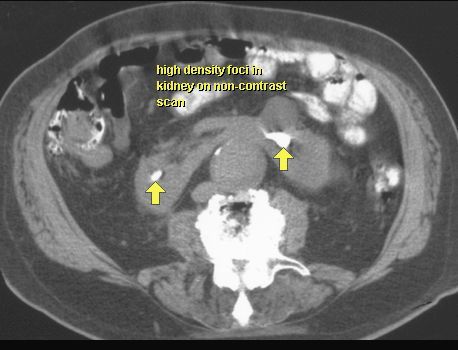

NERKA PODKOWIASTA

TK